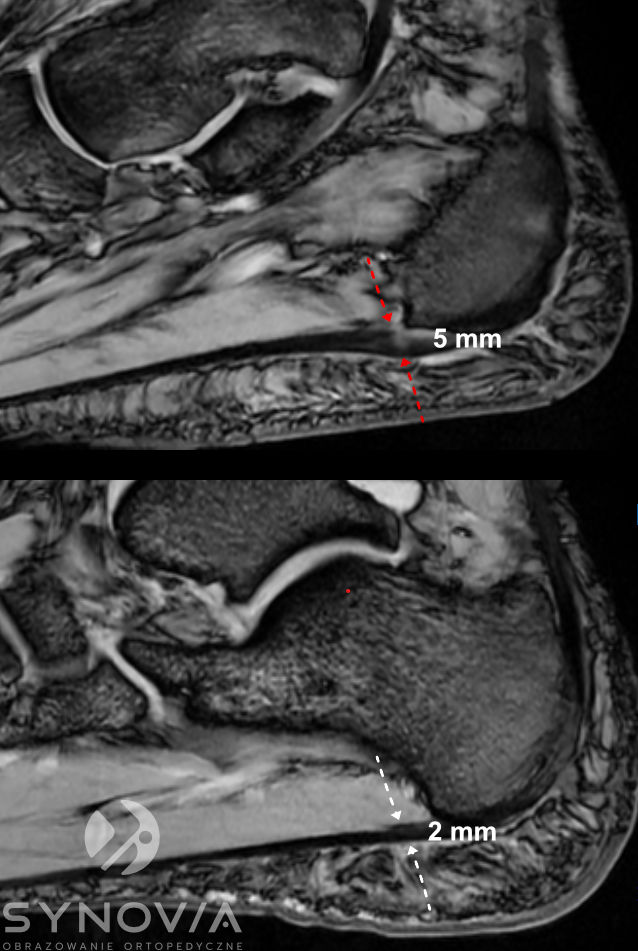

MRI

Co widać: Szczegółowa ocena powięzi, obrzęk szpiku kostnego w kości piętowej, przydatne w różnicowaniu przyczyn.

Co widać: Stopień uszkodzenia ścięgna, obrzęk w kości piętowej, stan tkanek okolicznych, możłiwy dokładny monitoring gojenia, w tym gojenia pooperacyjnego.